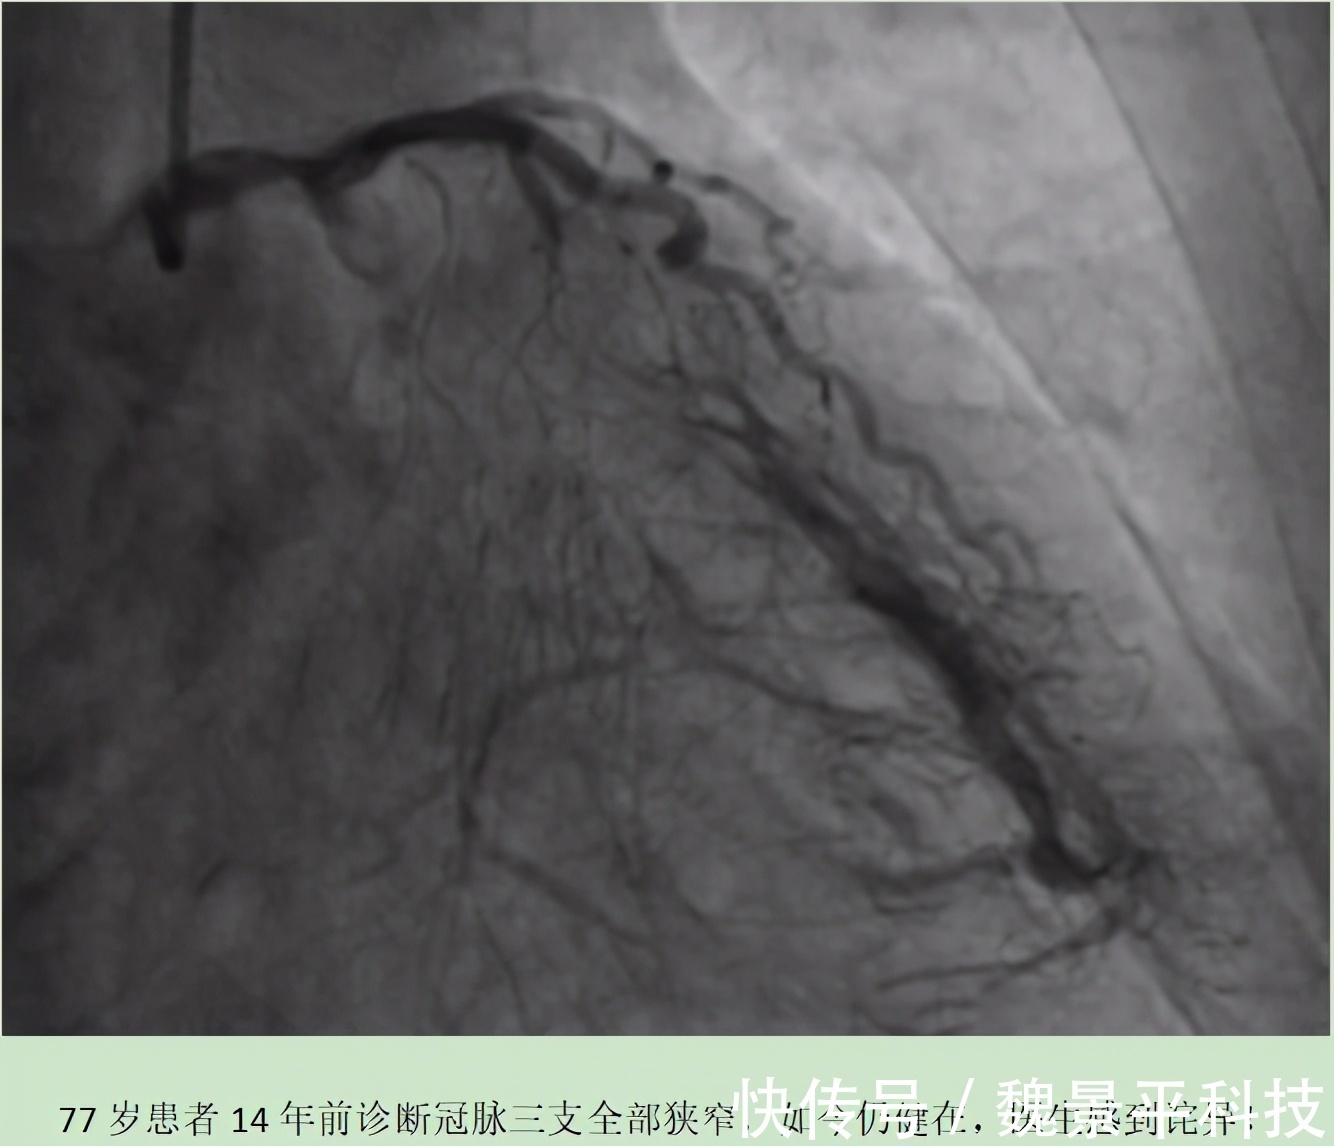

老马凭什么能活到现在?医生第一次听到老马诉说10多年前的就诊经历,总觉得不可思议。照他所说,那时候他的冠状动脉三支全部都堵了,要知道这可是负责心脏供血的主血管,如果真如此的话,很难想象他还能活到现在,而且谁也看不出这是一位曾经被判了死刑的病人。所以,医生对老马的印象格外深刻。事实证明,老马说的全都是真的。因为在后来一次复查时,老马做了冠脉造影检查,结果发现他的冠状动脉三支仍存在进展性狭窄病变。只不过,在三支主血管的周围也生出了庞大的分支系统,有些分支血管足够强大,甚至超过了主血管。简单来说,老马的心脏成功建立了侧支循环。所以,在负责心脏供血的冠状动脉被堵时,侧支循环就开始发力,并取而代之,成为心脏供血供氧的主力。这或许就是老马能健康地活到现在的主要原因。